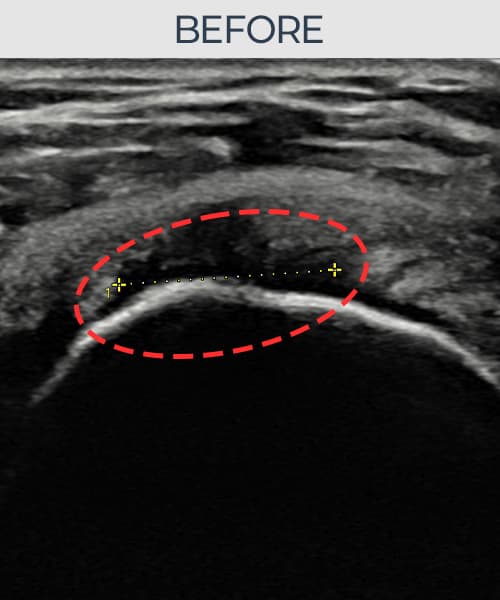

[経過期間: 23.07.31~23.09.27]

[縫縮術] 超音波検査にて左 棘上筋腱 부착부 광범위 部分断裂(13mm × 5mm (腱厚の約65%欠損))を確認。縫縮術施行後、腱の連続性が回復し、日常生活に復帰されました。